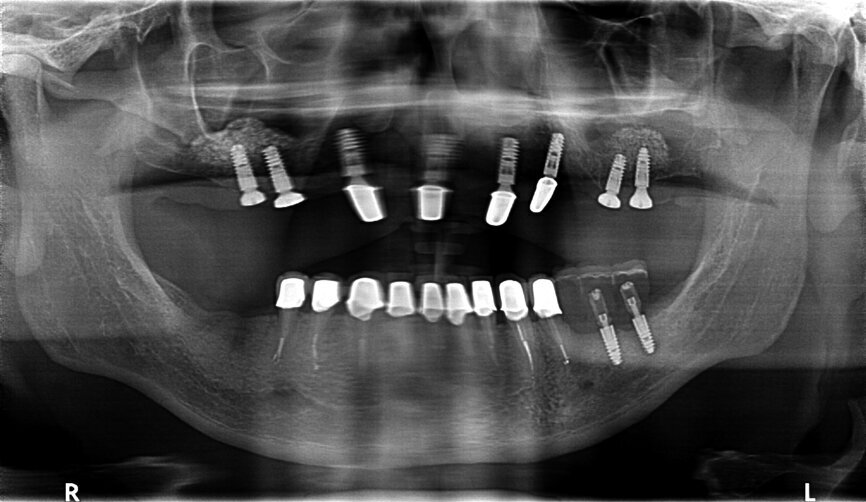

Fig. 30: OPG after placing implants.

Fig. 31: OPG after exposing implants at the lateral section and having used a temporary prosthesis based on telescopes.

Fig. 32: OPG after treatment.

If the quality of the work satisfies our expectations, we may proceed to the handing-over stage and perform the functional and aesthetic analysis, both intra- and extraorally. A perfect conclusion to the treatment process is the receipt of a complete set of OPG X-rays taken before, during and following treatment (Figs. 29–32).